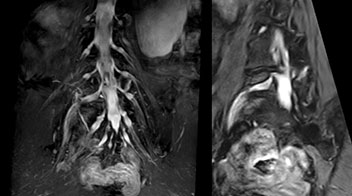

Northern Fukushima Medical Center (NFMC) Imaging Center uses the 3D NerveVIEW sequence for performing MR neurography, particularly in patients with pain and weakness in the lower limb. “It is included in about 20% of the approximately 150 lumbar spine MRI exams each month at NFMC, and can help us to determine if structures are impinging on the nerves,” says Hajime Tanji, RT, MRI technologist at NFMC.

“Although symptoms of typical disc herniation and atypical hernia are very similar, the actual site of herniation is different. It is therefore important to characterize the nerve’s condition both inside and outside of the intervertebral foramina. “Conversely, if we see no abnormality in NerveVIEW, we can assume at least that there is no severe condition that requires surgery. Like this, it can help us avoid unnecessary surgery. NerveVIEW can have a tremendous impact in this way.”

“NerveVIEW is really useful for those cases where a nerve disorder is strongly suspected based on the clinical examination but our regular MRI images do not show any findings. These atypical herniations and spinal canal stenosis, occurring in 5% to 15% of the total lumbar herniation/stenosis cases are our main target when using NerveVIEW,” says Dr. Yabuki.

The addition of the nerve-selective NerveVIEW sequence to its spine MRI protocol has given NFMC competitive advantages, according to Tanji. “Since we started including NerveVIEW routinely, the demand for lumbar spine MRI examinations has increased, especially for pre-surgical planning purposes and for patients with chronic lower extremity symptoms,” he says. “Moreover, because no other hospitals in our region are doing nerve plexus imaging yet, we often receive referrals for MR neurography studies from other hospitals even if they have an MRI scanner. Some requests come from as far as 100 km away. NerveVIEW definitely provides us a competitive advantage.” “Based on our experience, we can certainly recommend NerveVIEW to other centers,” Dr. Yabuki adds. “The sequence opens up many possibilities to facilitate the diagnosis of lower extremity pain and to inform our decision-making regarding therapy and surgery.”